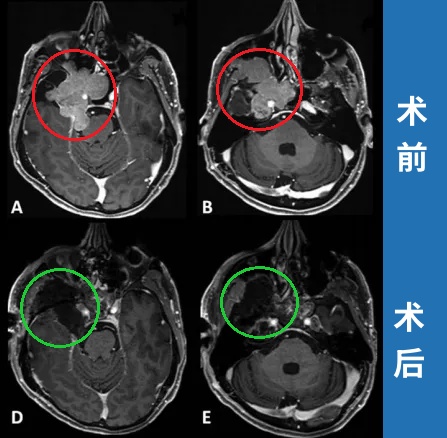

术前影像显示:

(A) 轴位T1加权钆增强MRI显示脑膜瘤延伸至后颅窝、海绵窦、眼眶和蝶窦

(B) 肿瘤延伸至中颅窝、翼腭窝和颞下窝

肿瘤位于颅底深处,被颈内动脉、海绵窦和脑干等重要结构包绕。INC国际神经外科顾问团成员、WFNS颅底手术委员会前主席Sebastien Froelich教授采用显微镜+神经内镜双镜联合技术完成脑膜瘤全切。

术前及术后MRI对比显示肿瘤完全切除。